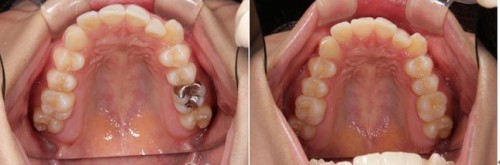

術前術後です。奥歯の銀歯が気になるとの患者様でしたが、このようにセラミックインレーに変更しましたが、大変喜ばれました。